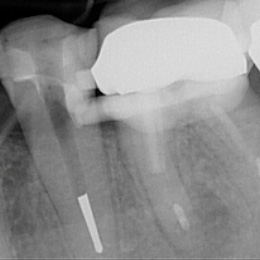

Fallbeispiel: Molarenrevision mit Seitenkanal

Werden im Rahmen einer Wurzelkanalbehandlung nicht alle Bereiche innerhalb des Wurzelkanalsystems ausreichend gereinigt, kann es zu persistierenden Infektionen kommen. In diesem Fall war die persistierende Infektion auf einen feinen Seitenkanal zurückzuführen – mit einer Revisionsbehandlung und gründlicher Reinigung des Wurzelkanalsystems können auch solche persistierenden Infektionen erfolgreich behandelt werden!